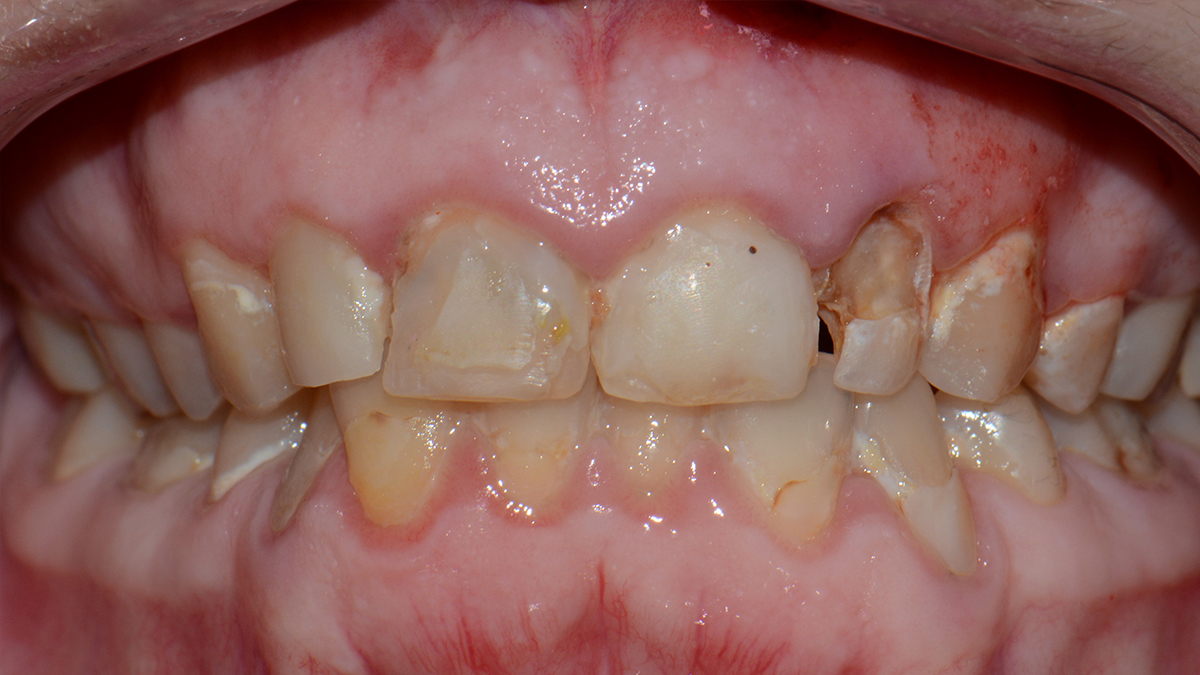

Sajnos a nem megfelelő szájhigiénia és-vagy nem megfelelő táplálkozás fogszuvasodás kialakulásához vezethet. Ennek terápiája a fertőzött, szuvas foganyag eltávolításával, majd a fog tömőanyaggal vagy betéttel való helyreállításával lehetséges.

Fogaink külső felszínét szervezetünk legkeményebb anyaga, a zománc borítja. A zománc 98%-át szervetlen anyagok alkotják, amelyek savhatásra képesek kioldódni. Ez a magyarázata annak, hogy egy ilyen kemény anyag képes meggyengülni, sőt üreg képződhet pusztán baktériumok és szénhidrát hatására. Abban az esetben, ha a kórokozók átjutottak a zománc rétegen, a fogszuvasodás terjedése felgyorsulhat , ilyenkor általában már panaszos a fog, hidegre, édesre intenzívebben reagál.